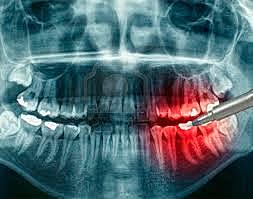

• Radiología oral y maxilofacial

Radiología oral y maxilofacial

La radiologia oral y maxilofacial fue reconocida como una especialidad odontológica por la Asociación Dental Americana.